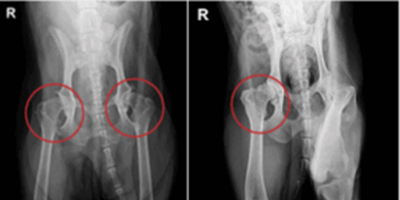

인공 고관절 치환술 Total Hip Replacement (THR) 고관절

고관절 인공관절 수술은 고관절 이형성증, 대퇴두 무혈성 괴사, 외상성 고관절 탈구 등으로 관절이 비가역적으로 손상된 경우에 시행됩니다.

FHO(Femoral Head Ostectomy)와 같은 보존적 또는 대체 수술만으로는 충분한 기능 회복이 어려운 경우, 통증 완화와 정상적인 관절 기능 회복을 위해 인공 고관절 치환술이 효과적인 선택이 될 수 있습니다.